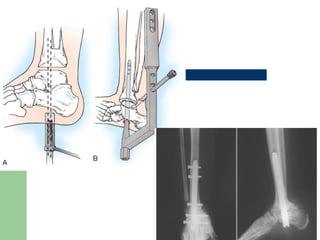

Surgical treatment Ankle:  Arthrodesisof ankle to place the foot Plantigrade.  IM nail/Charnley/Ilizarov External Fixators  Average time for Fusion:20 months(IM nail).  Talus -- fragmented and avascular--talectomy and tibiocalcaneal arthrodesis.